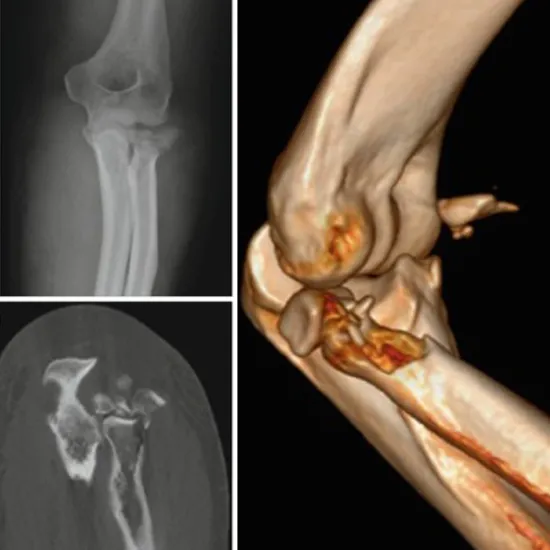

3D CT Right Elbow is an imaging scan to visualize the bony assessment of the right elbow in 3D reconstruction.

You need to lie on his/her back on the CT table and the right elbow is placed in the center of the gantry and is extended palm facing upward and the opposite arm is placed on the side after proper positioning of the elbow scan is performed and the image is reconstructed in 3D to detect the problem.